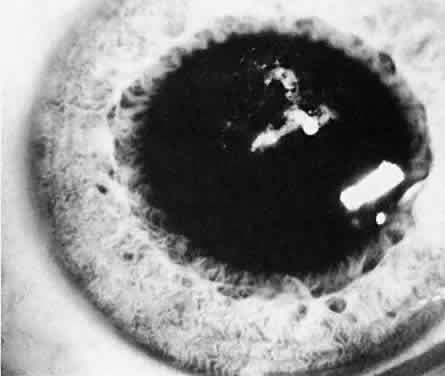

Usually, anterior polar cataracts are visually insignificant and allow normal visual development (see Fig. 1). However, some affect vision, and all require careful monitoring.7 Centrally located cataracts that are on or near the posterior lens capsule have a greater effect on the refraction of light and visual acuity (Fig. 2). Nuclear cataracts associated with metabolic disorders or prenatal infections produce double refracting systems that cause optical distortion and significantly decrease visual acuity (Fig. 3).